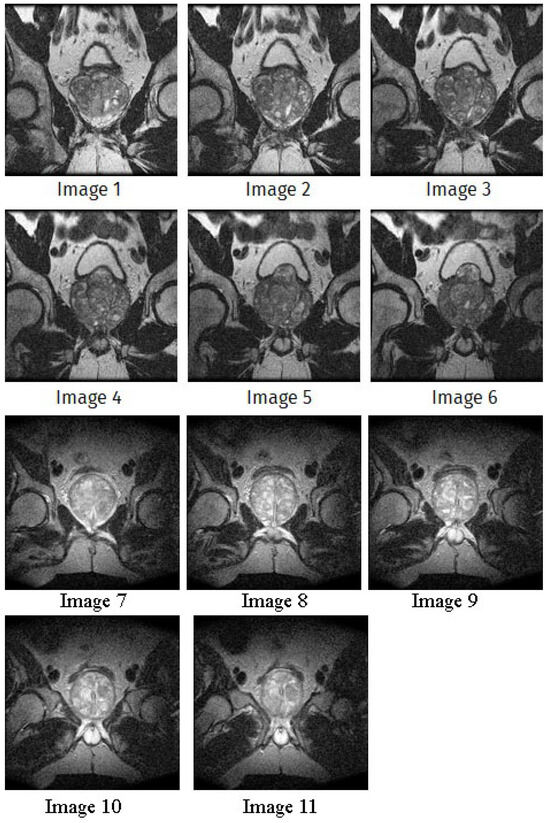

| Image | nt = 3 | nt = 4 | nt = 5 | nt = 8 |

|---|---|---|---|---|

| 1 | ![]() | ![]() | ![]() | ![]() |

| 2 | ![]() | ![]() | ![]() | ![]() |

| 3 | ![]() | ![]() | ![]() | ![]() |

| 4 | ![]() | ![]() | ![]() | ![]() |

| 5 | ![]() | ![]() | ![]() | ![]() |

| 6 | ![]() | ![]() | ![]() | ![]() |

| 7 | ![]() | ![]() | ![]() | ![]() |

| 8 | ![]() | ![]() | ![]() | ![]() |

| 9 | ![]() | ![]() | ![]() | ![]() |

| 10 | ![]() | ![]() | ![]() | ![]() |

| 11 | ![]() | ![]() | ![]() | ![]() |